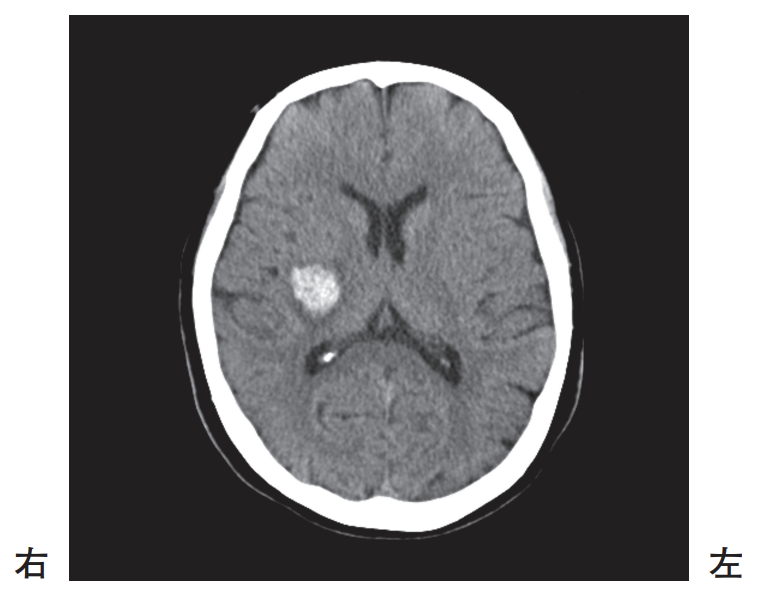

頭部単純CT

65歳の男性。入浴中、軽度の意識障害および左片麻痺が突然出現したため救急車で搬送された。救急外来到着時の頭部単純CTを別に示す。

考えられるのはどれか。